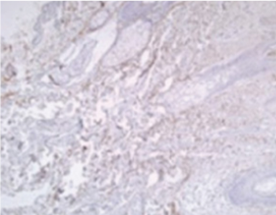

02. 프로테오글리칸 제공

프로테오글리칸을 제공하여 탄탄함과 수분 보충을 돕고 피부 구조 개선의 효과를 볼 수 있습니다.

• radiesse_img08

시술 전

• radiesse_img09

시술 후